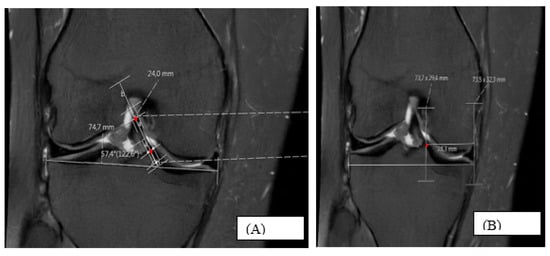

Morphometric Evaluation of Anterior Cruciate Ligament Orientation and Tibial Footprint Location Using Magnetic Resonance Imaging

Background/Objectives: The anterior cruciate ligament (ACL) plays a key role in knee stability, biomechanics, and proprioception, and is one of the most frequently injured and reconstructed ligaments in both athletes and the general population. The anatomical placement of femoral and tibial tunnels close to the native ACL insertion sites is critical for long-term clinical outcomes and graft survival. This study aimed to define sagittal and coronal ACL alignment and tibial footprint morphology on magnetic resonance imaging (MRI) in healthy knees, to explore sex- and side-related differences, and to provide population-specific reference values. Methods: In this retrospective cross-sectional study, knee MRIs acquired between 2018 and 2021 were screened, and knees with an intact ACL and without deformity or joint pathology that could alter alignment were included. After applying inclusion and exclusion criteria, 636 knees (320 right, 316 left) from 545 individuals (338 women, 298 men; 15–80 years, mean age 34.87 ± 11.65 years) were analyzed. On sagittal images, the sagittal ACL angle (S-ANGLE) was measured on the slice where the ligament appeared maximally visualized. The midpoints of the ACL were identified on two adjacent sagittal slices, and a line drawn through these midpoints was used to represent the central axis of the ligament; the angle between this line and the tibial plateau was recorded as the S-ANGLE. For anteroposterior localization of the tibial footprint, an anteroposterior reference distance (S-long) was defined as the length measured parallel to the tibial plateau, extending from the midpoint of the tibial tuberosity (corresponding to the insertion site of the patellar ligament and used as a topographic anterior landmark) toward the posterior aspect of the proximal tibia. A perpendicular line was drawn from the anterior end of S-long to establish the anterior reference boundary. The distance from this anterior reference line to the midpoint of the ACL tibial footprint along the same anteroposterior axis was defined as S-short. The sagittal footprint percentage (S-PERCENTAGE) was calculated as (S-short/S-long) × 100, representing the size-normalized sagittal anteroposterior position of the ACL tibial footprint midpoint. On coronal images, the ACL–tibial plateau angle (C-ANGLE), mediolateral tibial length (C-long), and distance from the medial edge to the ACL insertion (C-short) were obtained; C-PERCENTAGE was calculated analogously. Medial mechanical proximal tibial angle (mMPTA) was used to confirm physiological coronal alignment. Non-parametric tests were applied, with p < 0.05 considered statistically significant. Results: Women had significantly greater sagittal ACL angles than men, whereas anteroposterior distances measured from the midpoint of the tibial tuberosity (used as an anterior topographic landmark) and oriented parallel to the tibial plateau (S-LONG) and mediolateral tibial lengths (C-LONG) and absolute distances to the ACL tibial footprint were larger in men. In contrast, normalized sagittal and coronal footprint percentages (S-PERCENTAGE, C-PERCENTAGE) did not differ meaningfully between sexes, indicating the preservation of the relative ACL tibial insertion site despite size differences. Small but statistically significant side-to-side differences were observed in some coronal parameters; however, absolute differences were small and did not substantially modify the overall alignment pattern. Conclusions: This study provides large-sample, population-specific reference values for ACL orientation and tibial footprint location in both sagittal and coronal planes in healthy knees. The combination of higher sagittal ACL angles and shorter anteroposterior distances reference measured from the midpoint of the tibial tuberosity and oriented parallel to the tibial plateau (S-LONG) in women may represent a structural substrate contributing to the higher ACL injury rates reported in females. The morphometric data presented here may assist in individualized ACL reconstruction planning, MRI-based assessment of tibial tunnel position, and the design of knee-related biomedical implants and devices. Full article